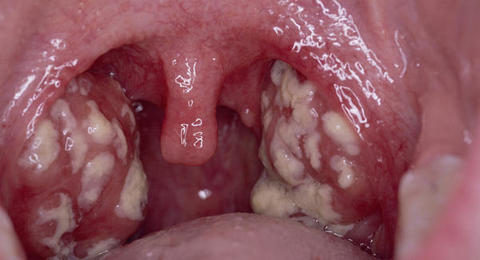

El médico hará una inspección de la boca y la garganta. Las amígdalas por lo general están enrojecidas y pueden tener manchas blancas. Los ganglios linfáticos en la mandíbula y el cuello pueden estar hinchados y sensibles al tacto.